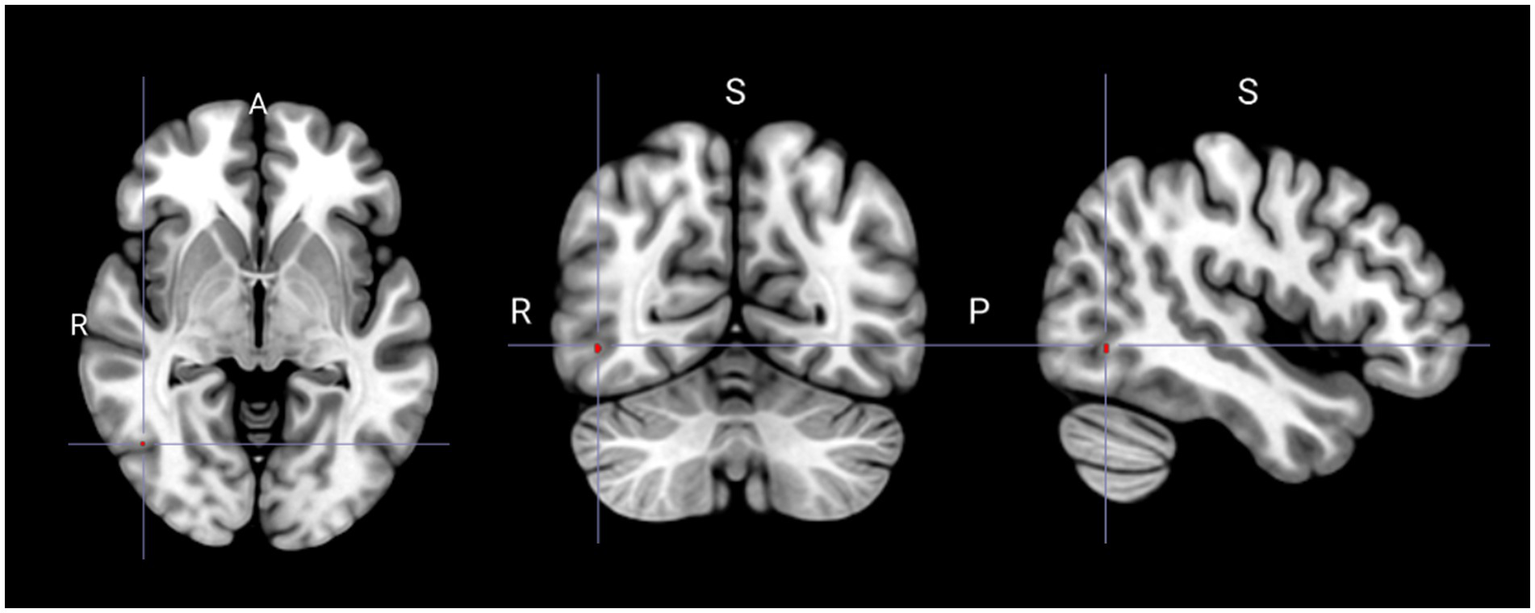

Compared with that in the non-PLC group, the PLC group exhibited significant hypometabolism in the right superior frontal gyrus (Figure 1; Table 2). Multiple regression analysis revealed that decreased metabolism in the right inferior or middle temporal gyri correlated with a higher PLACS score, indicating greater PLC severity (Figure 2; Table 3). No brain region showed a positive correlation.

Figure 2

Spatial distribution of reduced glucose metabolism correlated with increased severity of pathological laughing and crying (Puncorrected < 0.001). S, superior; R, right; P, posterior.